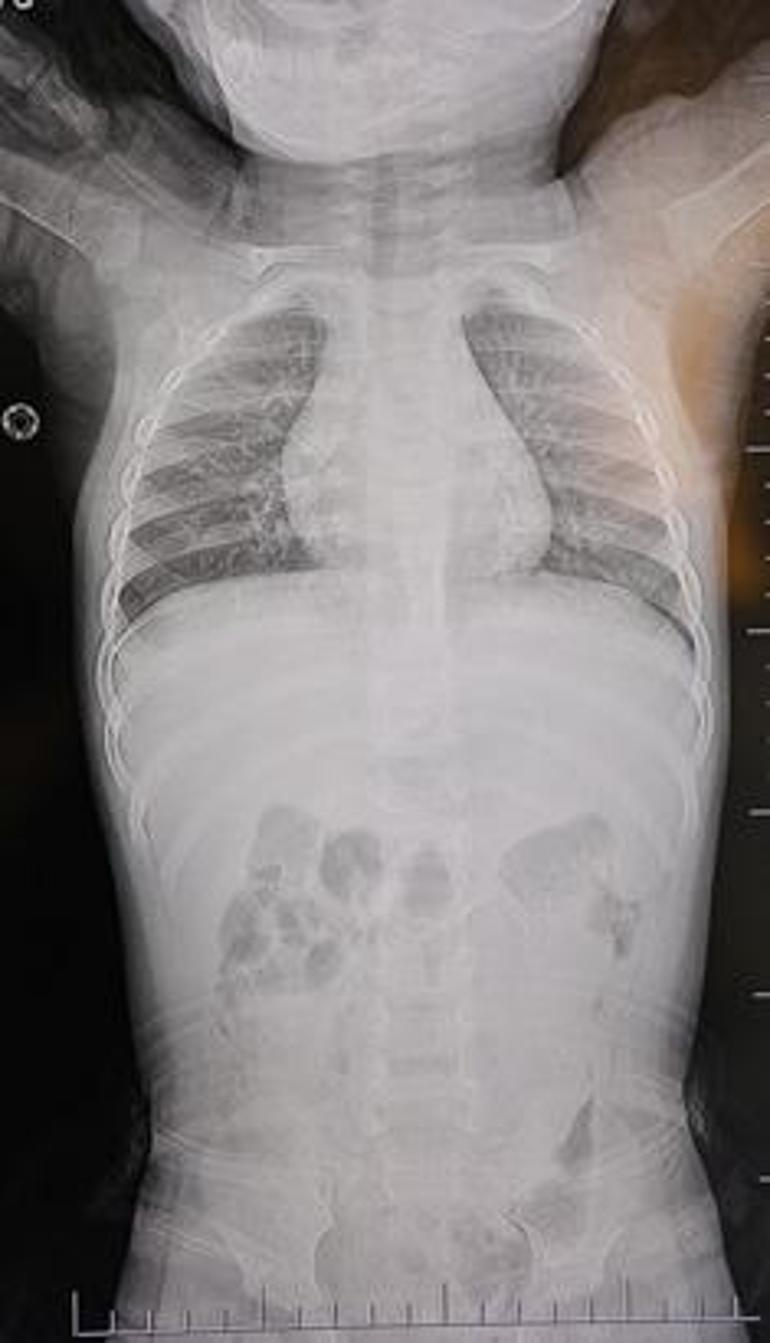

Bebeğin içinde ilerliyordu! 1 yıl boyunca ağladı: Tomografide korkunç gerçek

Kahramanmaraş’ta hastaneye götürülen bir yaşındaki bebeğin belinden akciğer zarına doğru ilerleyen 2 santimetrelik zımba teli çıktı. Aile, bebeğin doğduğundan beri zımba teli yüzünden rahatsızlık çektiğini belirterek sorumluların ceza almasını istedi.

Baba Poyraz, bir gün acil serviste yapılan kontrollerde bebeğin belinde yabancı cisim olduğunu, çekilen filmlerde ise “L” şeklinde zımba teli tespit edildiğini söyledi.

Poyraz, bebeğin doğduktan sonra sarılık diyerek kuvöze alındığını belirterek, “Bir hafta orada yattı. Sonra çıkardılar, eve getirdik. Eve geldikten sonra gece gündüz ağlaması hiç durmadı. Tekrar hastaneye götürdüm. Kaşınıyordu, bir hafta banyo yaptıramadık. Sonra duş aldırdım, bağırması daha da arttı. Belini açtık, sırtına baktık, bir şey var mı diye kontrol ettik, görünürde yoktu. Hastaneye götürdük, şurup verdiler. Aylar geçti. Daha sonra acilde bir doktor çocuğumun belinde yabancı cisim olduğunu söyledi. 184’ü aradım, şikayette bulundum. Başhekim yardımcısının yönlendirmesiyle tomografi çekildi. O zaman belinde zımba teli olduğu netleşti. Başka bir hastaneye götürdük, ‘riskli, 8 yaşına kadar alınamaz’ dediler, geri gönderdiler. Eve geldikten üç gün sonra oğlum bayıldı. Kardeşimle özel hastaneye götürdük. Orada filmlere baktılar, ‘akciğere doğru gidiyor, L şeklinde zımba teli var, alınması lazım’ dediler” dedi.